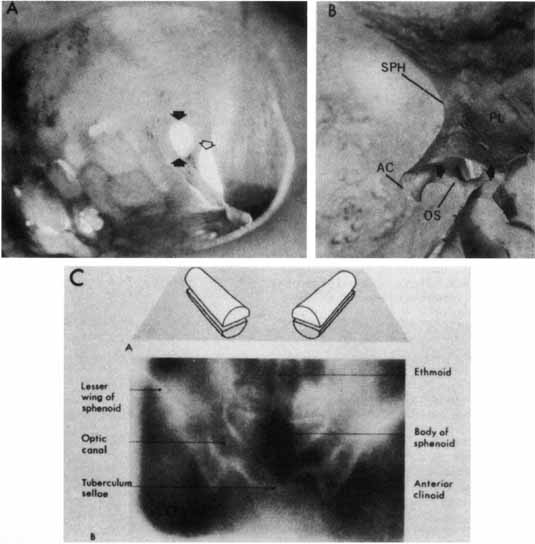

The optic canal runs posteromedially in the spheroid bone, at an angle of approximately 35° with the midsagittal plane (Fig. 5). The optic canal is 4 to 10 mm in length and contains not only the optic nerve but also the ophthalmic artery, branches of the carotid sympathetic plexus, and extensions of the intracranial meninges that form the sheaths of the optic nerve. The aural covering of the nerve and the periosteum of the canal are fused, but the arachnoid is continuous, permitting the subarachnoid space of the optic nerves to communicate freely with the intracranial subarachnoid space, both of which contain cerebrospinal fluid.

Fig. 5 The optic canal. A. Anterior view of left orbital apex. Orbital end of optic canal is vertically oval (black arrows) and separated from superior orbital fissure (open arrow) by optic strut. Note transilluminated ethmoidal and sphenoidal air cells, which form medial orbital wall and medial wall of optic canal. B. Posterior view of intracranial aspect of left optic canal demonstrating horizontally oval contour. The optic strut (OS) forms the ventrolateral margin of the canal and separates it from the carotid artery. In this preparation the ethmoidal and sphenoidal air cells have been opened. AC, anterior clinoid; PL, planum; SPH, sphenoidal wing. C. Tomographic section of optic canals in upper diagram. Normal axial tomogram below. (Illustration C from Harwood-Nash DC: Optic gliomas and pediatric neuroradiology. Radiol Clin North Am 10:83, 1972)

The mesial surface of the optic canal protrudes into the superolateral aspect of the spheroid sinus, and according to Fujii and colleagues,52 the optic nerves are separated from the sinus cavity by only the nerve sheath and mucosa in some 4% of specimens; in 78%, less than a 0.5-mm thickness of bone separates the optic nerves from the sinus cavity. Manipulations at the lateral spheroid sinus wall during transsphenoidal surgical procedures may damage the optic nerves.